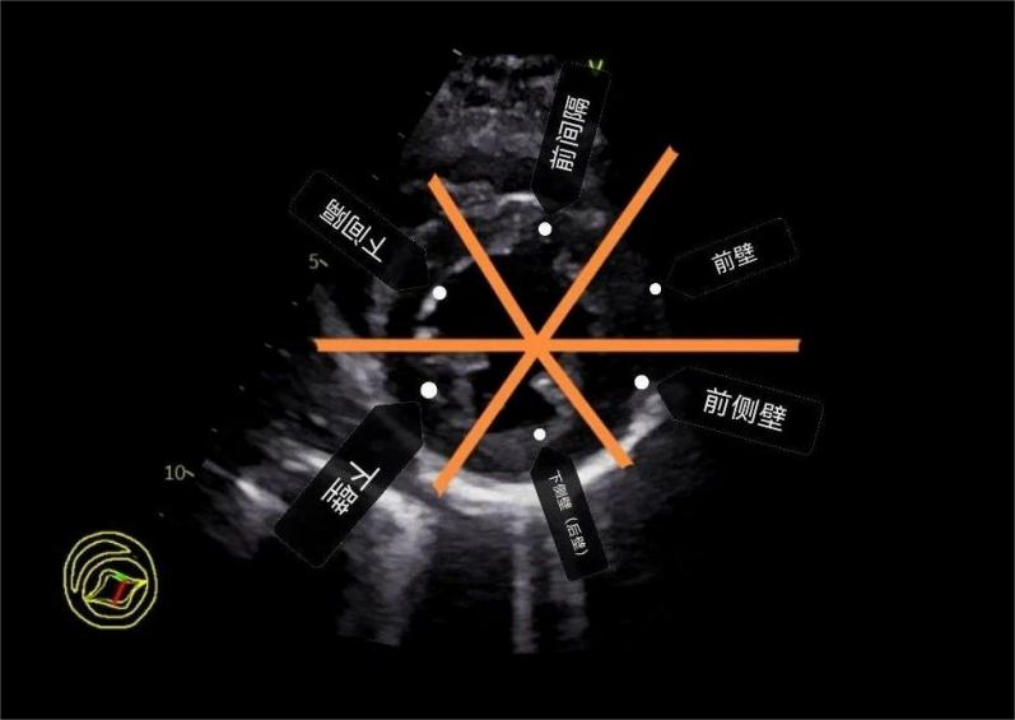

心梗最典型的超声表现就是心肌节段性运动异常。

此外并发症还有室壁瘤形成,血栓形成,室间隔穿孔甚至心脏破裂等。